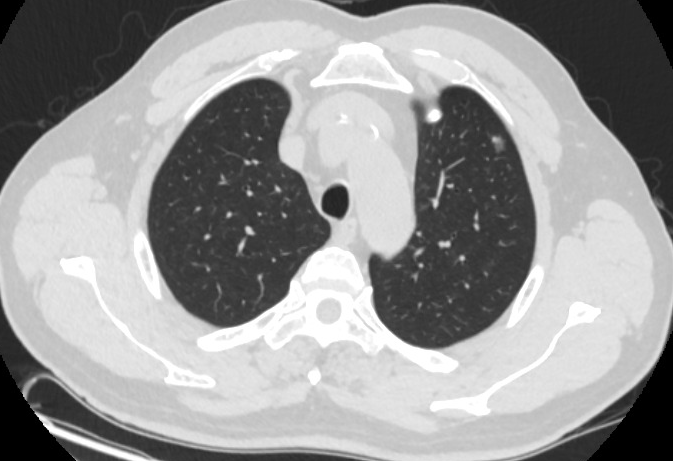

肺结节病,虽然是良性,但是有两个风险。

"大家好,肺结节病虽然查出是良性,但也不能掉以轻心,因为等于身上背了一个“不定时炸弹”,大家一定要注意起来。肺结节有两个风险。

1.增大风险,结节逐渐增大,可能会压迫到呼吸系统和我们的肺,出现咳血、发热、全身乏力、身体消瘦、食欲减退、呼吸困难、呼吸衰竭等症状。

肺结节病

2.恶变风险,良性结节不管大小,都可能因为某些因素,出现恶变风险,恶变到一定程度就是我们俗称的肺癌。

所以说,查出肺结节即使是良性,咱也要尽早调理,使它缩小慢慢治疗,后期可彻底治愈。